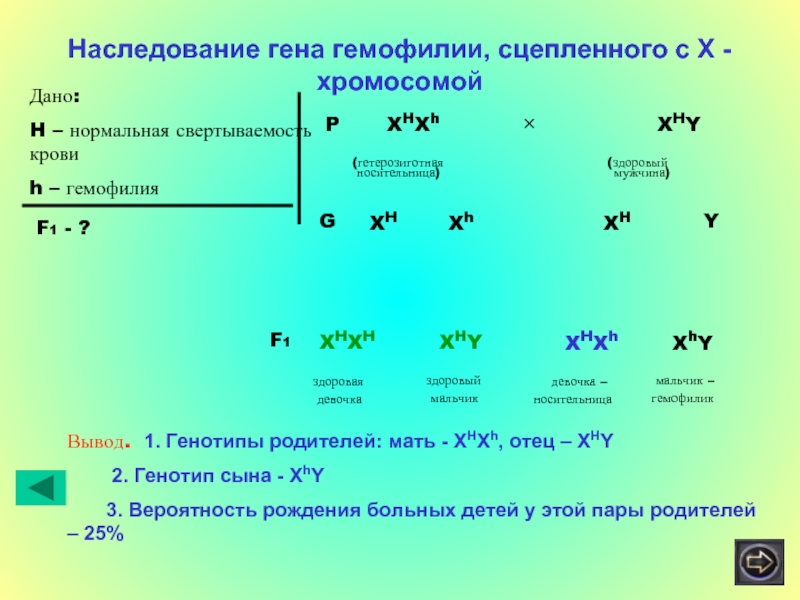

Генетика гемофилии: рецессивные гены и их проявления